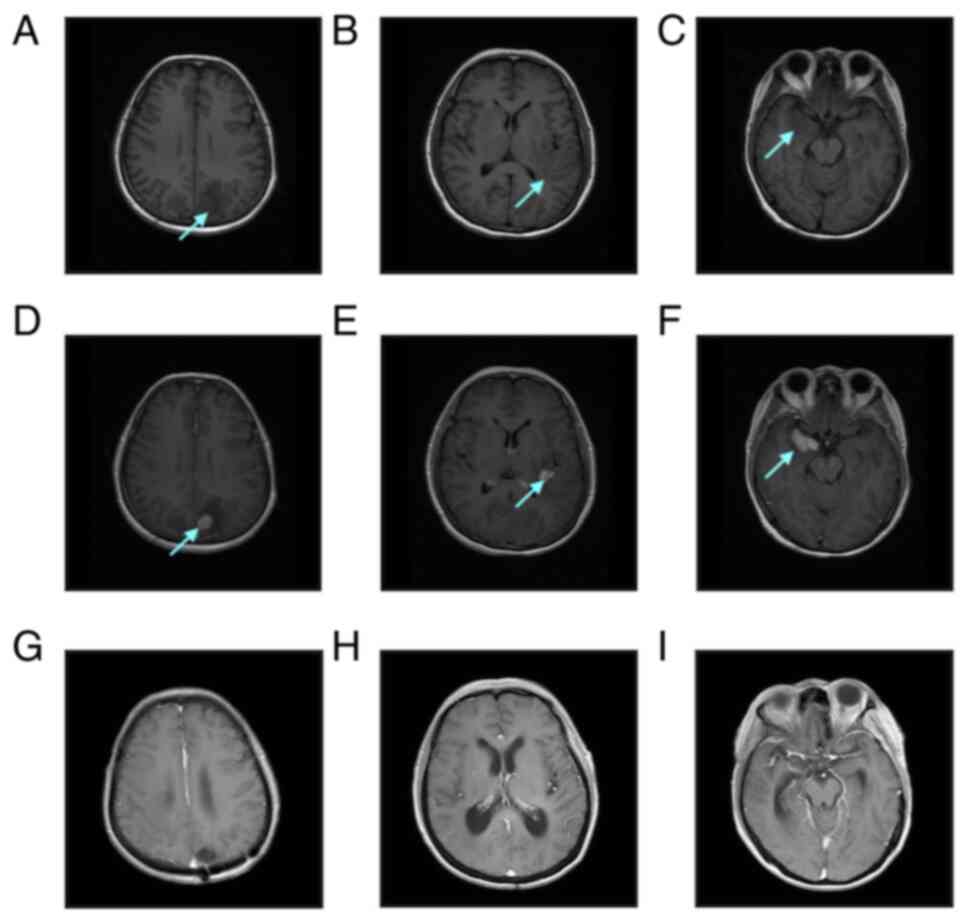

In April 2020, a 65-year-old woman presented to The Affiliated Hospital of Yangzhou University (Yanzhou, China) with a persistent headache that had lasted for >10 days. The patient had a history of hypertension of >10 years, but no personal or familial history of neurological disorders or genetic disorders, and no recent history of drug use. On admission, the blood pressure was 158/89 mmHg and vital signs were stable. No abnormalities were observed on cardiopulmonary, abdominal or neurological examination. Laboratory tests suggested that the results of routine blood and blood biochemical examinations were normal. Serum tests for human immunodeficiency virus (HIV), Epstein-Barr virus (EBV)-DNA, HHV8, hepatitis B and hepatitis C were negative. Cranial magnetic resonance imaging (MRI) showed multiple soft-tissue masses of varying sizes in both parietal lobes, the left basal ganglia and both temporal lobes, with a maximum size of ~3.1×2.1 cm, surrounded by irregular edematous signals and slightly narrowed adjacent ventricles, sulci and cisterns (Fig. 1A-F). Whole-body positron emission tomography-computed tomography (PET/CT) results suggested multiple mixed density shadows in the brain, abnormally increased fluorodeoxyglucose metabolism and a maximum standardized uptake value value of 29.6, indicating the presence of a tumor. No significant abnormalities were found in other parts of the body. A left parieto-occipital intracerebral tumor resection, expanded meningeal repair and cranioplasty were performed in April 2020, at 23 days post-admission. Immunohistochemical analysis (Data S1) revealed that the tumor cells were positive for CD19, CD79α, Bcl-2 (~92%), c-Myc (~50%), multiple myeloma oncogene 1 (Mum-1), lymphocyte common antigen and paired box protein 5, while showing negative results for CD20, CD10, CD38, CD56, CD138, Bcl-6, programmed cell death protein 1 (PD-1), programmed cell death receptor 1 ligand 1 (PD-L1), Epstein-Barr encoding region, terminal deoxynucleotidyl transferase and ALK. Microscopic examination revealed scattered positivity for CD3 and CD8, but no CD4 signal. The Ki-67 proliferation index was >80%. In the tumor microenvironment, <10% of tumor-associated macrophages expressed PD-L1, with an intermediate intensity of positive cells. The number of PD-1-positive tumor-infiltrating lymphocytes (TILs) was 30–40 cells in the high-power field microscopy, and the intensity of positive cells was intermediate (Fig. 2 and Data S1). Next-generation sequencing (Data S1) of the brain tumor tissue showed a CD79B p.Y196C missense mutation at 77.64% variant allele frequency (VAF), as well as an MYD88 p.L265P missense mutation at 31.75% VAF, a TP53 p.R110P missense mutation at 20.41% VAF and an IGHD3-10-IGHJ3 gene rearrangement at 90.69% VAF. Fluorescence in situ hybridization (Data S1) of the tumor tissue was negative for the IGH/BCL-2, Bcl-6, c-Myc translocation and TP53 gene deletion. Upon examination of the peripheral blood, the gene rearrangement of IGH and TCR was negative. Morphological examination and flow cytometry (Data S1) of the bone marrow revealed no abnormalities. Additionally, a bone marrow biopsy showed no evidence of lymphoma. Based on these results, the patient was diagnosed with CD20-negative PCNSL that was double positive for c-Myc and Bcl-2.

Figure 1.

Pre-treatment and post-treatment MRI examinations of the patient. (A-C) Pre-contrast axial T1-weighted imaging revealed multiple patch-shaped hypo-intense shadows in both the parietal and temporal lobes, with blurred boundaries. (D-F) Post-contrast axial T1-weighted MRI showed multiple intense nodular mass enhancement shadows in both the parietal and temporal lobes. (G-I) After treatment with the Bruton tyrosine kinase inhibitor combined with the programmed cell death protein 1 monoclonal antibody regimen, post-contrast axial T1-weighted MRI showed the tumor lesion had disappeared and the surrounding patchy edema zone was no longer enhanced. The arrows show the tumor masses. MRI, magnetic resonance imaging.

First, the patient was treated with high-dose methotrexate (HD-MTX) at 3.0 g/m2 on day 1 and administered mannitol to lower cranial pressure, and analgesic symptomatic treatment. After the first cycle of HD-MTX, the patient's headache was not significantly relieved and was accompanied by limb weakness. A cranial MRI examination was performed again, revealing multiple irregular nodular enhancement shadows in both parietal lobes and the right temporal lobe, with more and larger lesions than had been previously observed, increased edema around some of the lesions, new right ventricular compression narrowing and a midline left deviation. The regimen was then adjusted to HD-MTX combined with cytarabine (Ara-c) and temozolomide chemotherapy at the following doses: 3.5 g/m2 MTX on day 1, 1.0 g/m2 Ara-c every 12 h on days 2 and 3, and 220 mg temozolomide every day on days 1–5. The patient's headache was relieved by this therapy. However, the headache worsened in the intervals between chemotherapy, accompanied by vomiting and a loss of vision. The patient experienced left-sided limb weakness and impaired voluntary walking; a physical examination revealed that the muscle strength of the left limb was at grade 3. A third cranial MRI was performed, and the results showed that both sides of the parietal occupancy were larger than before, the extent of the surrounding brain parenchymal edema had increased, and the right ventricle and lateral fissure pool were significantly compressed. On assessing the patient's symptoms and MRI results, it was concluded that the patient's disease was progressing. The treatment regimen was changed to a Bruton tyrosine kinase (BTK) inhibitor combined with a PD-1 inhibitor, specifically zanubrutinib at 320 mg/day and tislelizumab at 200 mg on day 1 for 21 days in one cycle. The patient's headache and limb weakness were significantly relieved. After two courses of treatment (5 months after the first admission), the results of the cranial MRI review suggested that the patient's disease had reached complete remission (CR) (Fig. 1G-I). The patient continued to receive the same regimen for consolidation and as maintenance treatment, and a cranial MRI was performed every 3 months. In the 20 months of follow-up since the CR diagnosis, the patient's condition has ultimately remained stable and the patient is in good general condition with no significant toxic side effects.